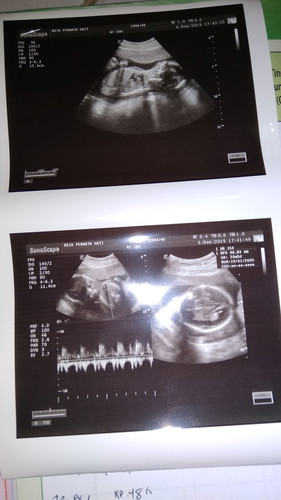

Baca lagiItu foto kanan garis 3 .. setahuku cewek , saya dulu sering antar sdr yg anaknya sdh 3 dan cewek semua ... klo garisnya 3 gt biasa cewek . Tp gk tau yah , di coba cari opini dr dktr lain aja bun biar lbh jls .